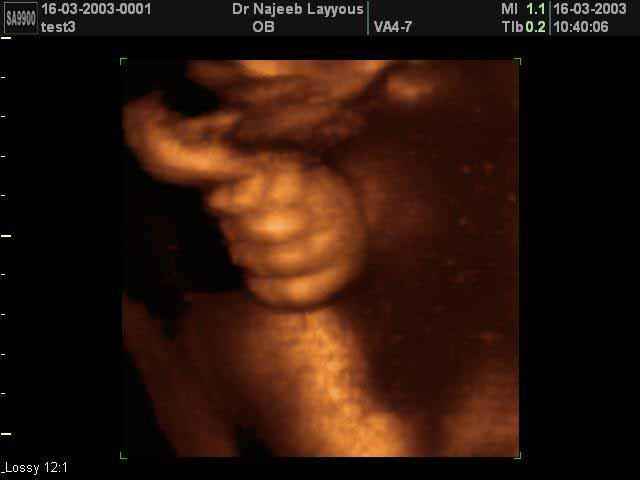

- 3D Fetal Limbs Ultrasound Scan Photos